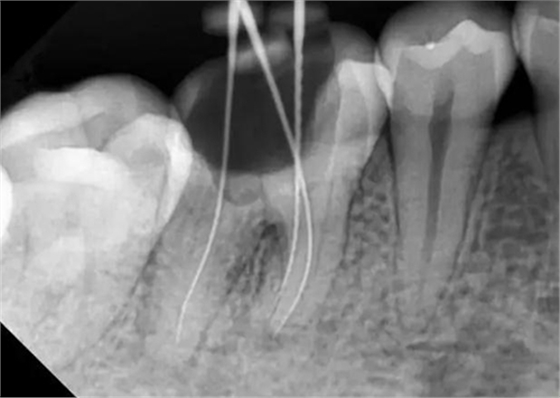

牙根內(nèi)外吸收的原因不同,治療方法和預(yù)后也不一樣。因此,應(yīng)根據(jù)X線和臨床表現(xiàn),區(qū)別內(nèi)外吸收,選擇適應(yīng)的治療方法,用X線根尖片和咬合片的表現(xiàn)區(qū)分牙根內(nèi)外吸收;內(nèi)吸收邊界清楚光滑,形狀多對(duì)稱,吸收部位根管粗大;外吸收邊界粗糙,密度不一,呈蠶食壯,形狀多不對(duì)稱,在破壞未穿通根管前,仍能尋找到根管的原始輪廓。偏移投照時(shí),內(nèi)吸收與根管的位置關(guān)系不變,而外吸收部位發(fā)生變化。

內(nèi)吸收是從髓腔或根管內(nèi)壁開始,與牙髓炎癥和細(xì)菌感染有關(guān)。一般無癥狀,多為X線照相時(shí)發(fā)現(xiàn)。應(yīng)盡早行根管治療,去除感染組織后,預(yù)后良好,否則進(jìn)一步發(fā)展會(huì)造成根管壁的穿孔。徹底去除內(nèi)吸收部位的感染組織較為困難,充分沖洗或超聲蕩洗是有效的清潔方法,并在根管內(nèi)封Ca(OH)2蝴劑1周后再根充。由于內(nèi)吸收過大,根管壁很薄,應(yīng)避免過大壓力,要選用Ca(OH)2基質(zhì)的蝴劑與牙膠根充,根管壁穿孔較小,可用 Ca(OH)2糊劑根充3個(gè)月,誘導(dǎo)硬組織形成后再根充;或用根管水泥(MTA)根管內(nèi)根充并修補(bǔ)。較大的根管壁穿孔可用MTA從根管內(nèi)或手術(shù)修補(bǔ)。內(nèi)吸收近根尖區(qū)可考慮根尖手術(shù),多根牙可考慮截根術(shù)。

牙根外吸收是從牙周組織開始,原因多為創(chuàng)傷,矯正力過大,埋伏牙,牙齒漂白,再植牙和根尖周炎癥等。因根尖周炎造成的根尖區(qū)外吸收處理方法同內(nèi)吸收,其他因素造成的外吸收采用相應(yīng)的對(duì)因處理和根管治療。